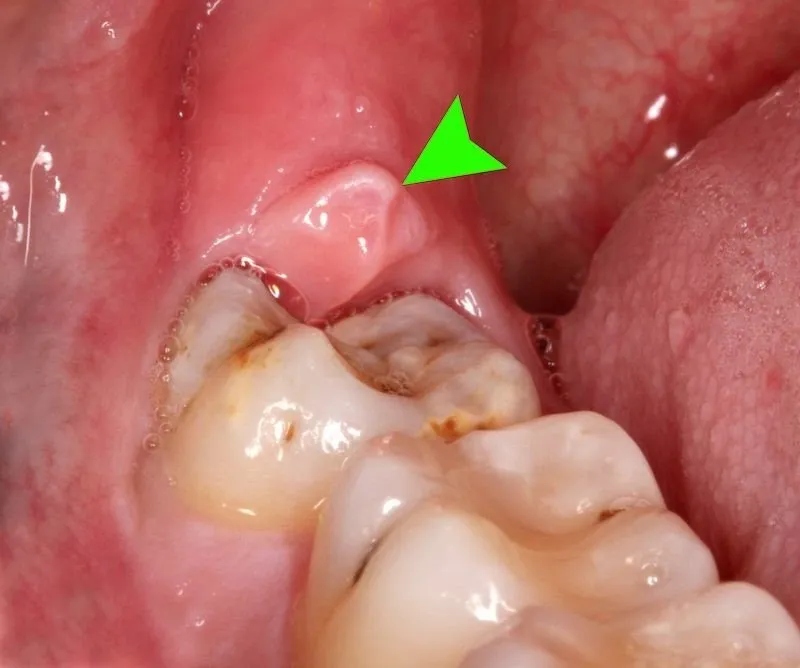

Hình ảnh viêm lợi trùm

Để giúp các bạn biết rõ bênh viêm lợi trùm, Nha khoa DrGreen xin gửi tới các bạn hình ảnh viêm lợi trùm chi tiết. Thông qua đó các bạn có thể nắm rõ và điều trị kịp thời. Cụ thể như sau:

Trên đây là những hình ảnh viêm lợi trùm rõ nhất mà bạn cần biết. Cùng với đó là nguyên nhân và cách điều trị hiệu quả bệnh này. Để được tư vấn cụ thể, hãy liên hệ Nha khoa DrGreen theo thông tin bên dưới